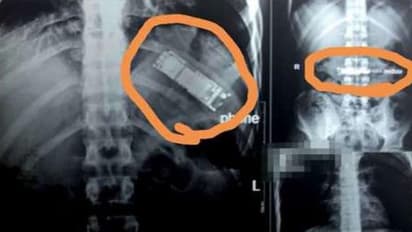

हटके  डेस्क: दुनिया में आपको कई तरह के लोग मिल जाएंगे। कुछ की बेवकूफी की कोई लिमिट ही नहीं होती। इन दिनों प्रैंक के नाम पर आपको कई तरह के अजीबोगरीब  काम करते लोग दिख जाएंगे। ये लोग मशहूर होने के लिए बेहद अजीब तरह के टास्क करते हैं। ऐसे ही एक प्रैंक के चक्कर में इजिप्ट में रहने वाले एक शख्स को मौत का सामना करना पड़ गया। इस शख्स ने दोस्त के साथ एक प्रैंक किया जिसके चक्कर में मोबाइल फ़ोन उसके पेट में चला गया। मोबाइल निगलने के बाद उसने डॉक्टर के पास जाने की जगह उसे नेचुरल तरीके से बाहर निकालने की कोशिश की, लेकिन असफल हुआ। आखिरकार  महीने के बाद वो डॉक्टर के पास गया, जिसके बाद सर्जरी के जरिये उसके पेट से मोबाइल बाहर निकाला गया। पेट से इस हाल में निकला मोबाइल फ़ोन...

मामला इजिप्ट से सामने आया जहां एक शख्स प्रैंक के चक्कर में हर लिमिट क्रॉस कर गया। वो अपने दोस्त के साथ ये प्रैंक कर रहा था। इसमें वो मोबाइल को निगल कर उसकी घंटी दोस्त को अपने पेट से आते हुए सुनाना चाहता था।

लेकिन ये प्रैंक उसपर ही उल्टा पड़ गया। गलती से उसने सच में ही मोबाइल निगल ली। इसके बाद मोबाइल उसके पेट में जाकर अटक गया। फिर भी शख्स डॉक्टर के पास नहीं गया।

पेट से मोबाइल को बाहर निकालने के लिए शख्स ने कई घरेलू उपाय अपनाए। उसने घर के किचन में रखी चीजें खाई, ताकि मोबाइल पॉटी के जरिये बाहर आ जाए। लेकिन ऐसा नहीं हुआ।

आखिरकार सात महीने में जब मोबाइल उसके पेट में गलने लगा, तो उसे उसकी तकलीफ बढ़ी। उसने  तब जाकर डॉक्टर को दिखाने का फैसला किया। वो नॉर्थ कैरो के बेनहा प्रान्त के एक स्टेट अस्पताल गया।

वहां डॉ मोहम्मद अल जहर ने उसका अल्ट्रसाउंड करवाया। इसमें उन्होंने देखा कि शख्स के पेट में मोबाइल अटका हुआ था। उसके बाहर नेचुरल तरीके से निकलने का कोई चांस नहीं था।

शख्स की सर्जरी कर मोबाइल को बाहर निकाला गया। शख्स के घरवालों को भी इसकी कोई जानकारी नहीं थी। ऐसे में शख्स ने अपनी पहचान छिपाए रखने की रिक्वेस्ट की। फिलहाल इस मामले ने सबको हैरत में डाल दिया है।